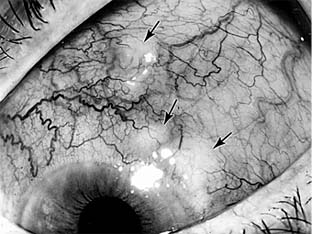

Reiter's disease affects men more frequently than women. The first attack of ocular inflammation usually consists of a self-limited papillary conjunctivitis. It follows, at a highly variable interval, the onset of nonspecific urethritis and the appearance of inflammation in one or more of the weight-bearing joints. Subsequent attacks of ocular inflammation may consist of acute iridocyclitis of one or both eyes, occasionally with hypopyon (Figure 16-4). Rheumatoid arthritis of adult onset may be accompanied by acute scleritis or episcleritis but very rarely by uveitis (Figure 16-5). (See also Chapter 7.)

Figure 16-5

Figure 16-5: Scleral nodules in a patient with rheumatoid arthritis. (Courtesy of S Kimura.)

Rheumatoid factor, an IgM autoantibody directed against the patient's own IgG, may play a major role in the pathogenesis of rheumatoid arthritis. The union of IgM antibody with IgG is followed by fixation of complement at the tissue site and the attraction of leukocytes and platelets to this area. An occlusive vasculitis, resulting from this chain of events, is thought to be the cause of rheumatoid nodule formation in the sclera as well as elsewhere in the body. The occlusion of vessels supplying nutrients to the sclera is thought to be responsible for the "melting away" of the scleral collagen that is so characteristic of rheumatoid arthritis (Figure 16-6).

Figure 16-6

Figure 16-6: Scleral thinning in a patient with rheumatoid arthritis. Note dark color of the underlying uvea.